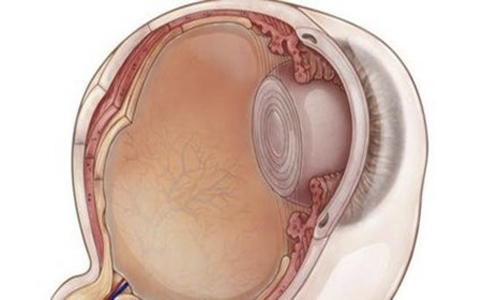

A:得了飛蚊症主要通過以下方法進行治療:1、藥物治療:藥物治療飛蚊症的療效不確切,飛蚊症又稱玻璃體混濁,可以分為生理性的玻璃體混濁和病理性的玻璃體混濁。對於生理性的玻璃體混濁,通常對患者的視力沒有特別的影響,一般不需要進行特殊治療,可以口服卵……

A:眼睛出現飛蚊,可以通過以下方法進行治療並緩解:1、藥物治療:藥物治療飛蚊療效並不確切,眼睛出現飛蚊又稱玻璃體混濁,可以分為生理性的玻璃體混濁和病理性的玻璃體混濁。生理性的飛蚊症,主要是由於隨著年齡的增加,玻璃體逐漸液化所導致,通常對患者的……